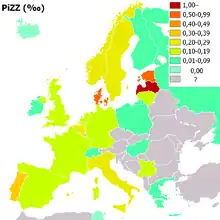

Serpin peptidase inhibitor, clade A, member 1 (SERPINA1) is the gene that encodes the protein alpha-1 antitrypsin. SERPINA1 has been localized to chromosome 14q32. Over 75 mutations of the SERPINA1 gene have been identified, many with clinically significant effects.[11] The most common cause of severe deficiency, PiZ, is a single base-pair substitution leading to a glutamic acid to lysine mutation at position 342 (dbSNP: rs28929474), while PiS is caused by a glutamic acid to valine mutation at position 264 (dbSNP: rs17580). Other rarer forms have been described .

People of Northern European and Iberian ancestry are at the highest risk for A1AD. Four percent of them carry the PiZ allele; between 1 in 625 and 1 in 2000 are homozygous.

Another study detected a frequency of 1 in 1550 individuals.[21] The highest prevalence of the PiZZ variant was recorded in the northern and western European countries with mean gene frequency of 0.0140.[21] Worldwide, an estimated 1.1 million people have A1AT deficiency and roughly 116 million are carriers of mutations.[21]